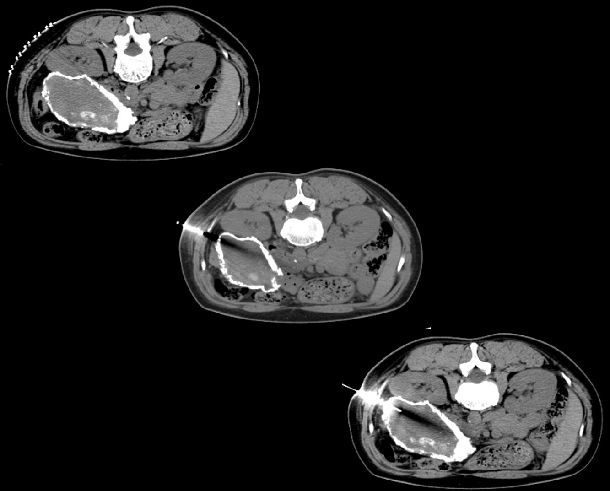

CT引导下穿刺活检(上图):穿刺组织呈黄色粘稠液性物质,不成形,经注射器抽出10ml黄色粘稠坏死物。穿刺病理结果提示:送检退变坏死物,未见健活细胞成分。

术后病理:送检胶原化纤维囊壁组织伴显著钙化,内壁附大量坏死物,未见健活成分。

综合病理及临床,考虑慢性坏死性胰腺炎可能性大。

关于胰腺病变穿刺活检:胰腺穿刺活检存在胰瘘继发腹膜炎风险,穿刺活检适应症选择较其他部位尤为严格。本病例术前CT显示胰腺体尾部正常胰腺组织消失,代之以不规则软组织密度病变,边缘可见环形钙化,经胰尾进针取体尾部病变组织不存在胰瘘风险。